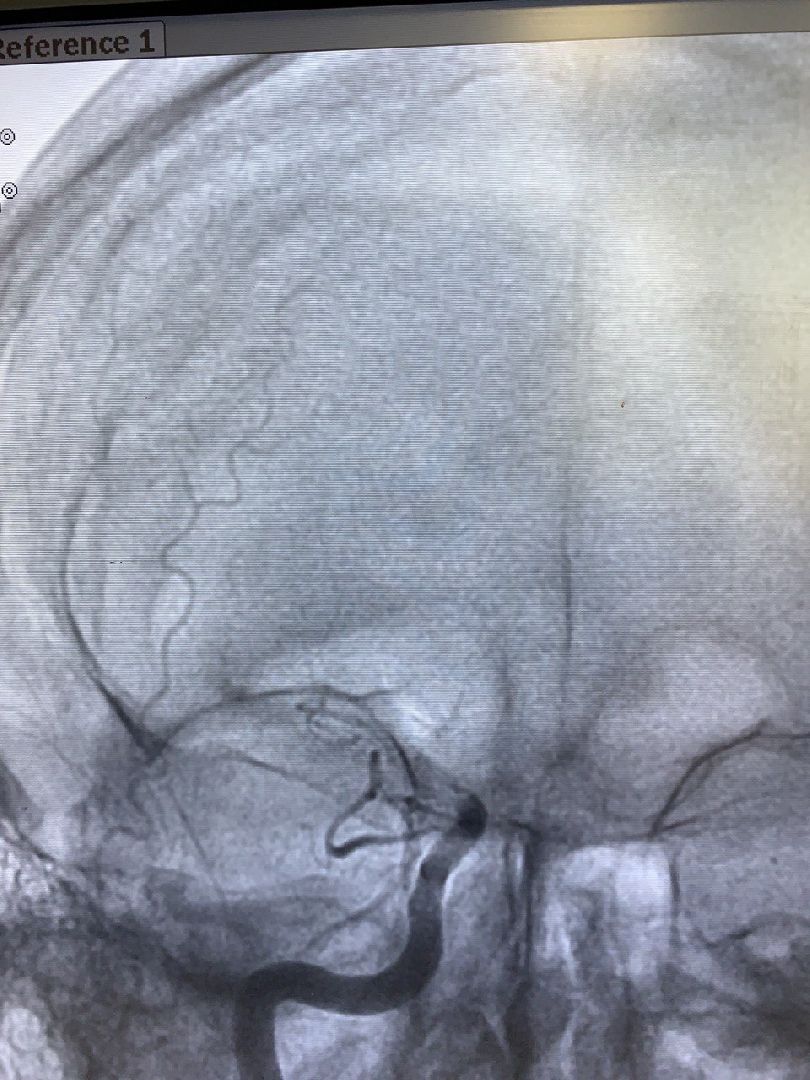

В Региональном сосудистом центре, который является частью Дмитровской областной больницы, освоили лечение ишемического инсульта методом эндоваскулярной ромбоэкстракции. Этим методом хирурги восстанавливают кровоток в пораженной артерии мозга.

Наряду с тромболизисом — растворением тромбов специальным препаратом — в региональном сосудистом центре теперь проводят процедуру тромбоэкстракции. Это высокотехнологичный метод извлечения тромбов из пораженных участков при помощи специальных инструментов.

Фото предоставлены Региональным сосудистым центром